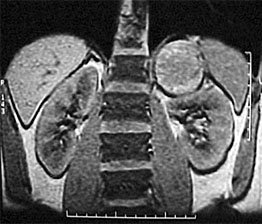

- Магнитно-резонансная томография брюшной полости и забрюшинного пространства без и с контрастным усилением (дает дополнительную информацию о распространенности и связи опухоли с окружающими органами).

Рисунок 2. КТ: опухоль при поступлении. Клинически: при пальпации опухоль в проекции правой почки до 12 см в диаметре. Общеклинические исследования в пределах возрастной нормы. При КТ органов брюшной и грудной полости: КТ-картина объемного образования правой почки без признаков интрапульмональных метастазов (см. рис. 2). УЗИ брюшной полости: в проекции правой почки солидно-кистозное образование 101ґ114ґ99 мм, объемом 500 мл, васкуляризация активная, интактная часть почки 57ґ12ґ40 мм. Объемное образование правой почки — опухоль Вильмса. Предварительный диагноз: опухоль Вильмса правой почки, 2-я стадия.